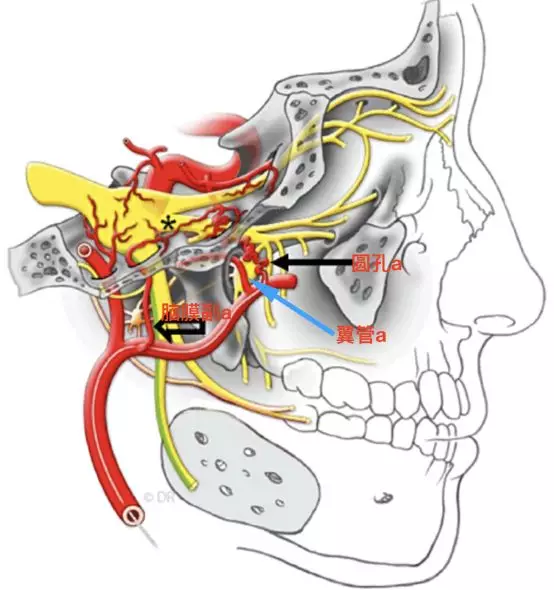

在颈内动脉起始段狭窄或者闭塞时,上颌内动脉翼腭段可能通过两个分支,对颈内动脉代偿供血。其一通过翼管动脉,经翼管至破裂孔,与颈内动脉岩段发出的翼管动脉吻合代偿供血。其二就是通过圆孔动脉,经圆孔入颅,在圆孔附近与颈内动脉海绵窦段发出的下外侧干形成代偿供血。

Tanoue等报道了一例颈内动脉近端闭塞,左侧颈外动脉CTA水平位重建,可观察到翼管动脉、圆孔动脉和腭鞘动脉等(Tanoue 2013)。

a,显示翼管动脉向后走行进入翼管(Tanoue 2013)。

b,腭鞘动脉,又称咽动脉(pharyngeal artery)发出紧邻翼管动脉,向后下方走行,与翼腭神经伴行,通过腭鞘管(咽管)(Tanoue 2013)。

圆孔动脉向后上走行,与上颌神经伴行,进入圆孔(Tanoue 2013)。圆孔位于翼管上方。